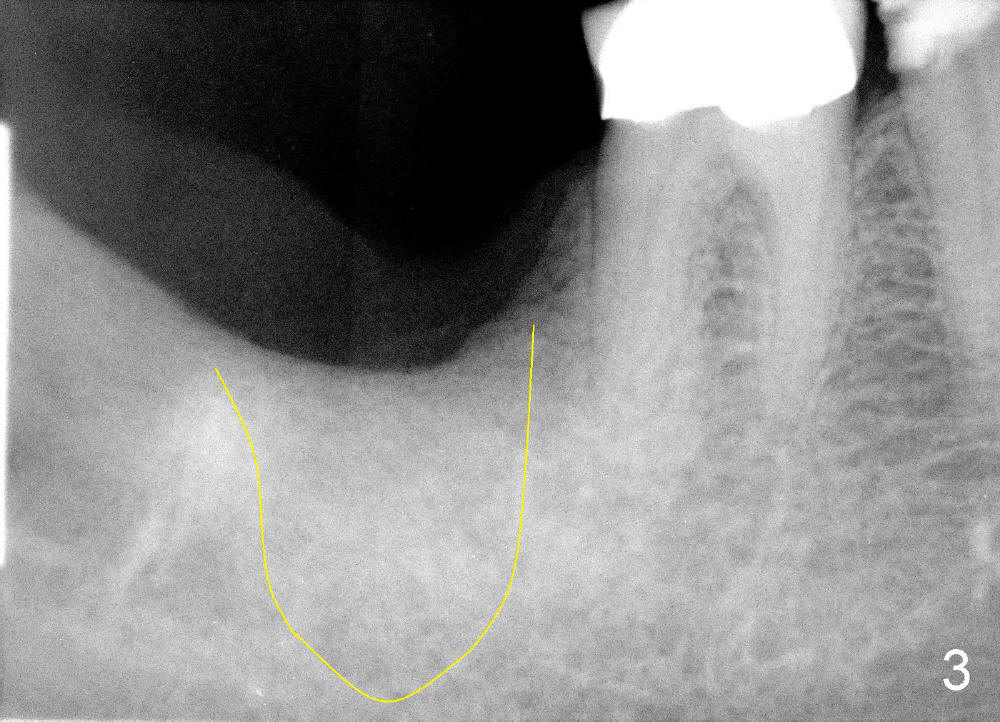

Mrs. Hwang in her sixties has had periodontal disease in her lower right 2nd molar (Fig.1 *). Three years later, both the 2nd and 3rd molars are extracted (Fig.2; pink: the upper border of the inferior alveolar canal). Four months after extraction, the patient returns for implant placement at the site of #31 (Fig.3, 4). The socket of the 2nd molar is outlined in yellow in Fig.3.